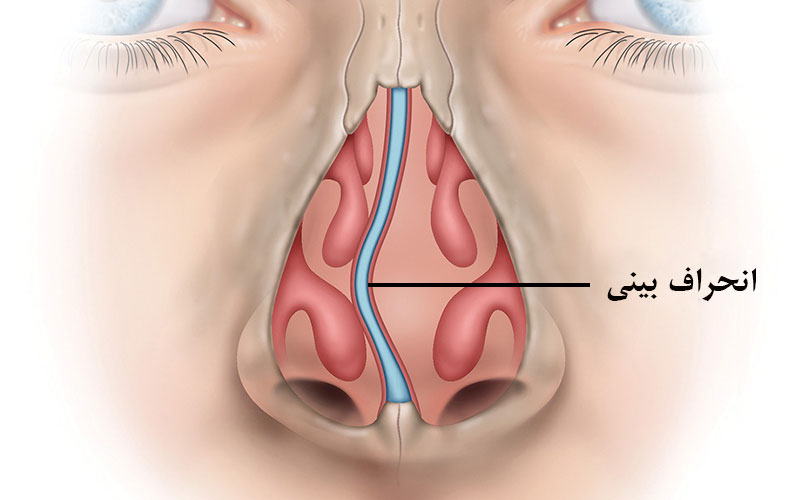

گوش و حلق و بینی